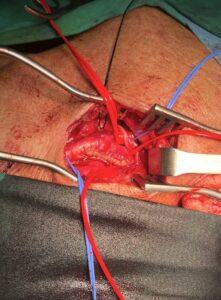

Ανοιχτή αποκατάσταση καρωτιδικής νόσου